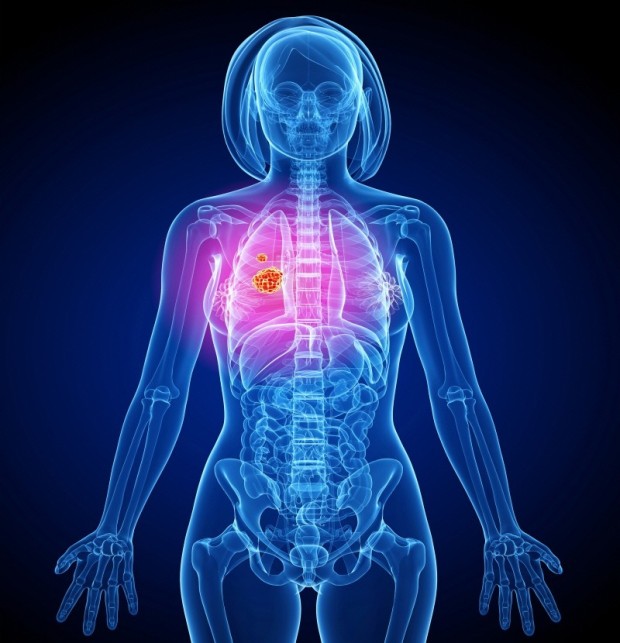

폐암은 위암, 갑상선암 다음으로 3번째로 발병 빈도가 높은 3대 암 중 한 가지인데요. 폐암은 재발과 전이까지의 빈도도 잦은지라 완치가 어렵다고 하며 폐암 발병 초기에는 거의 증상이 없을 수가 있어 수술이 불가능한 3기, 혹은 4기에 주로 진단된다고 해요.

폐암 초기증상 폐암 4기에 이르게 되면 5년 생존률이 30% 대로 감소하게 된다고 해요. 그리하여 폐암은 암 질병이자 중 사망자 비율이 가장 높은 것으로 나타나고 있어요.

폐암은 사망률 2위를 차지하고 있는 간암에 비해 무려 2배에 가까운 사망률을 보이고 있다고 합니다. 이렇게 치명적인 폐암에 대해 미리 알고 대처하는 것이 바람직할 것 같아요. 아래에서는 폐암이라 판단해 볼 수 있는 그 초기증상에 대해 간단히 설명드릴게요.